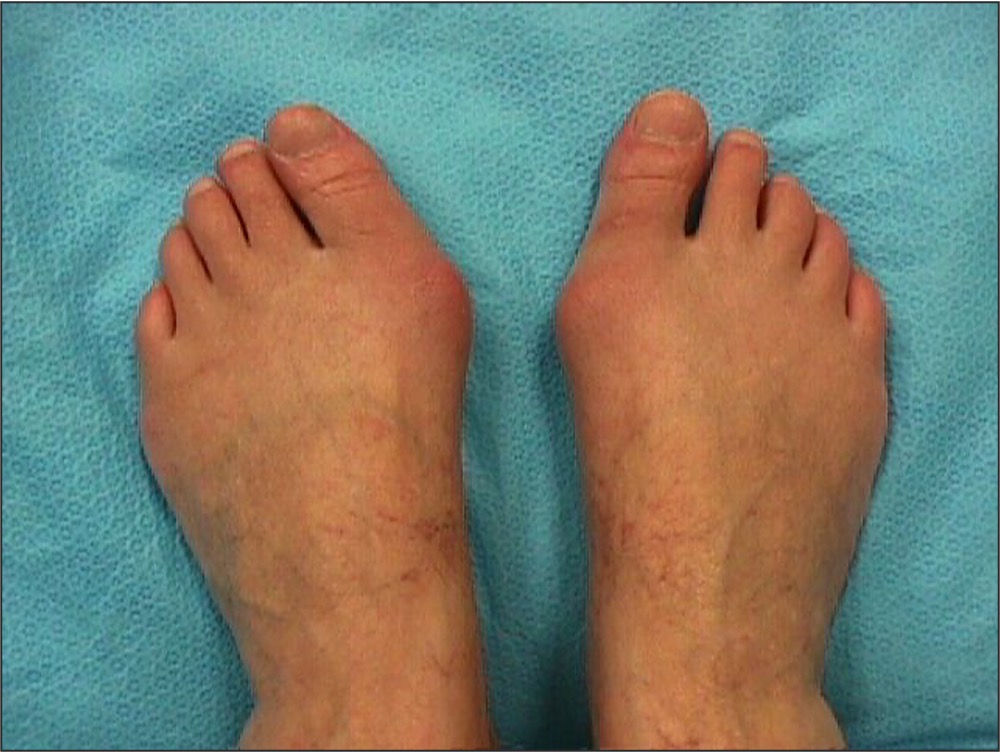

Examination

Great toe

- lateral deviation of the great toe

- medial deviation of the first metatarsal

- hallux pronation

- prominent mediation eminence

Lesser toes

- overriding of the second toe

- lesser toe hammer & claw